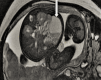

Figure 2

formation kystique, bien limitée à paroi propre en hyposignal T1 et hypersignal T2, venant au contact intime des anses digestives sur leur versant mésentérique